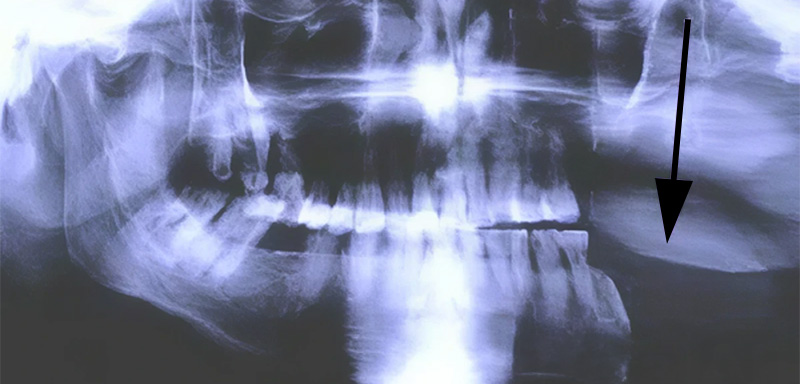

Fig. 02.

Fig. 02.